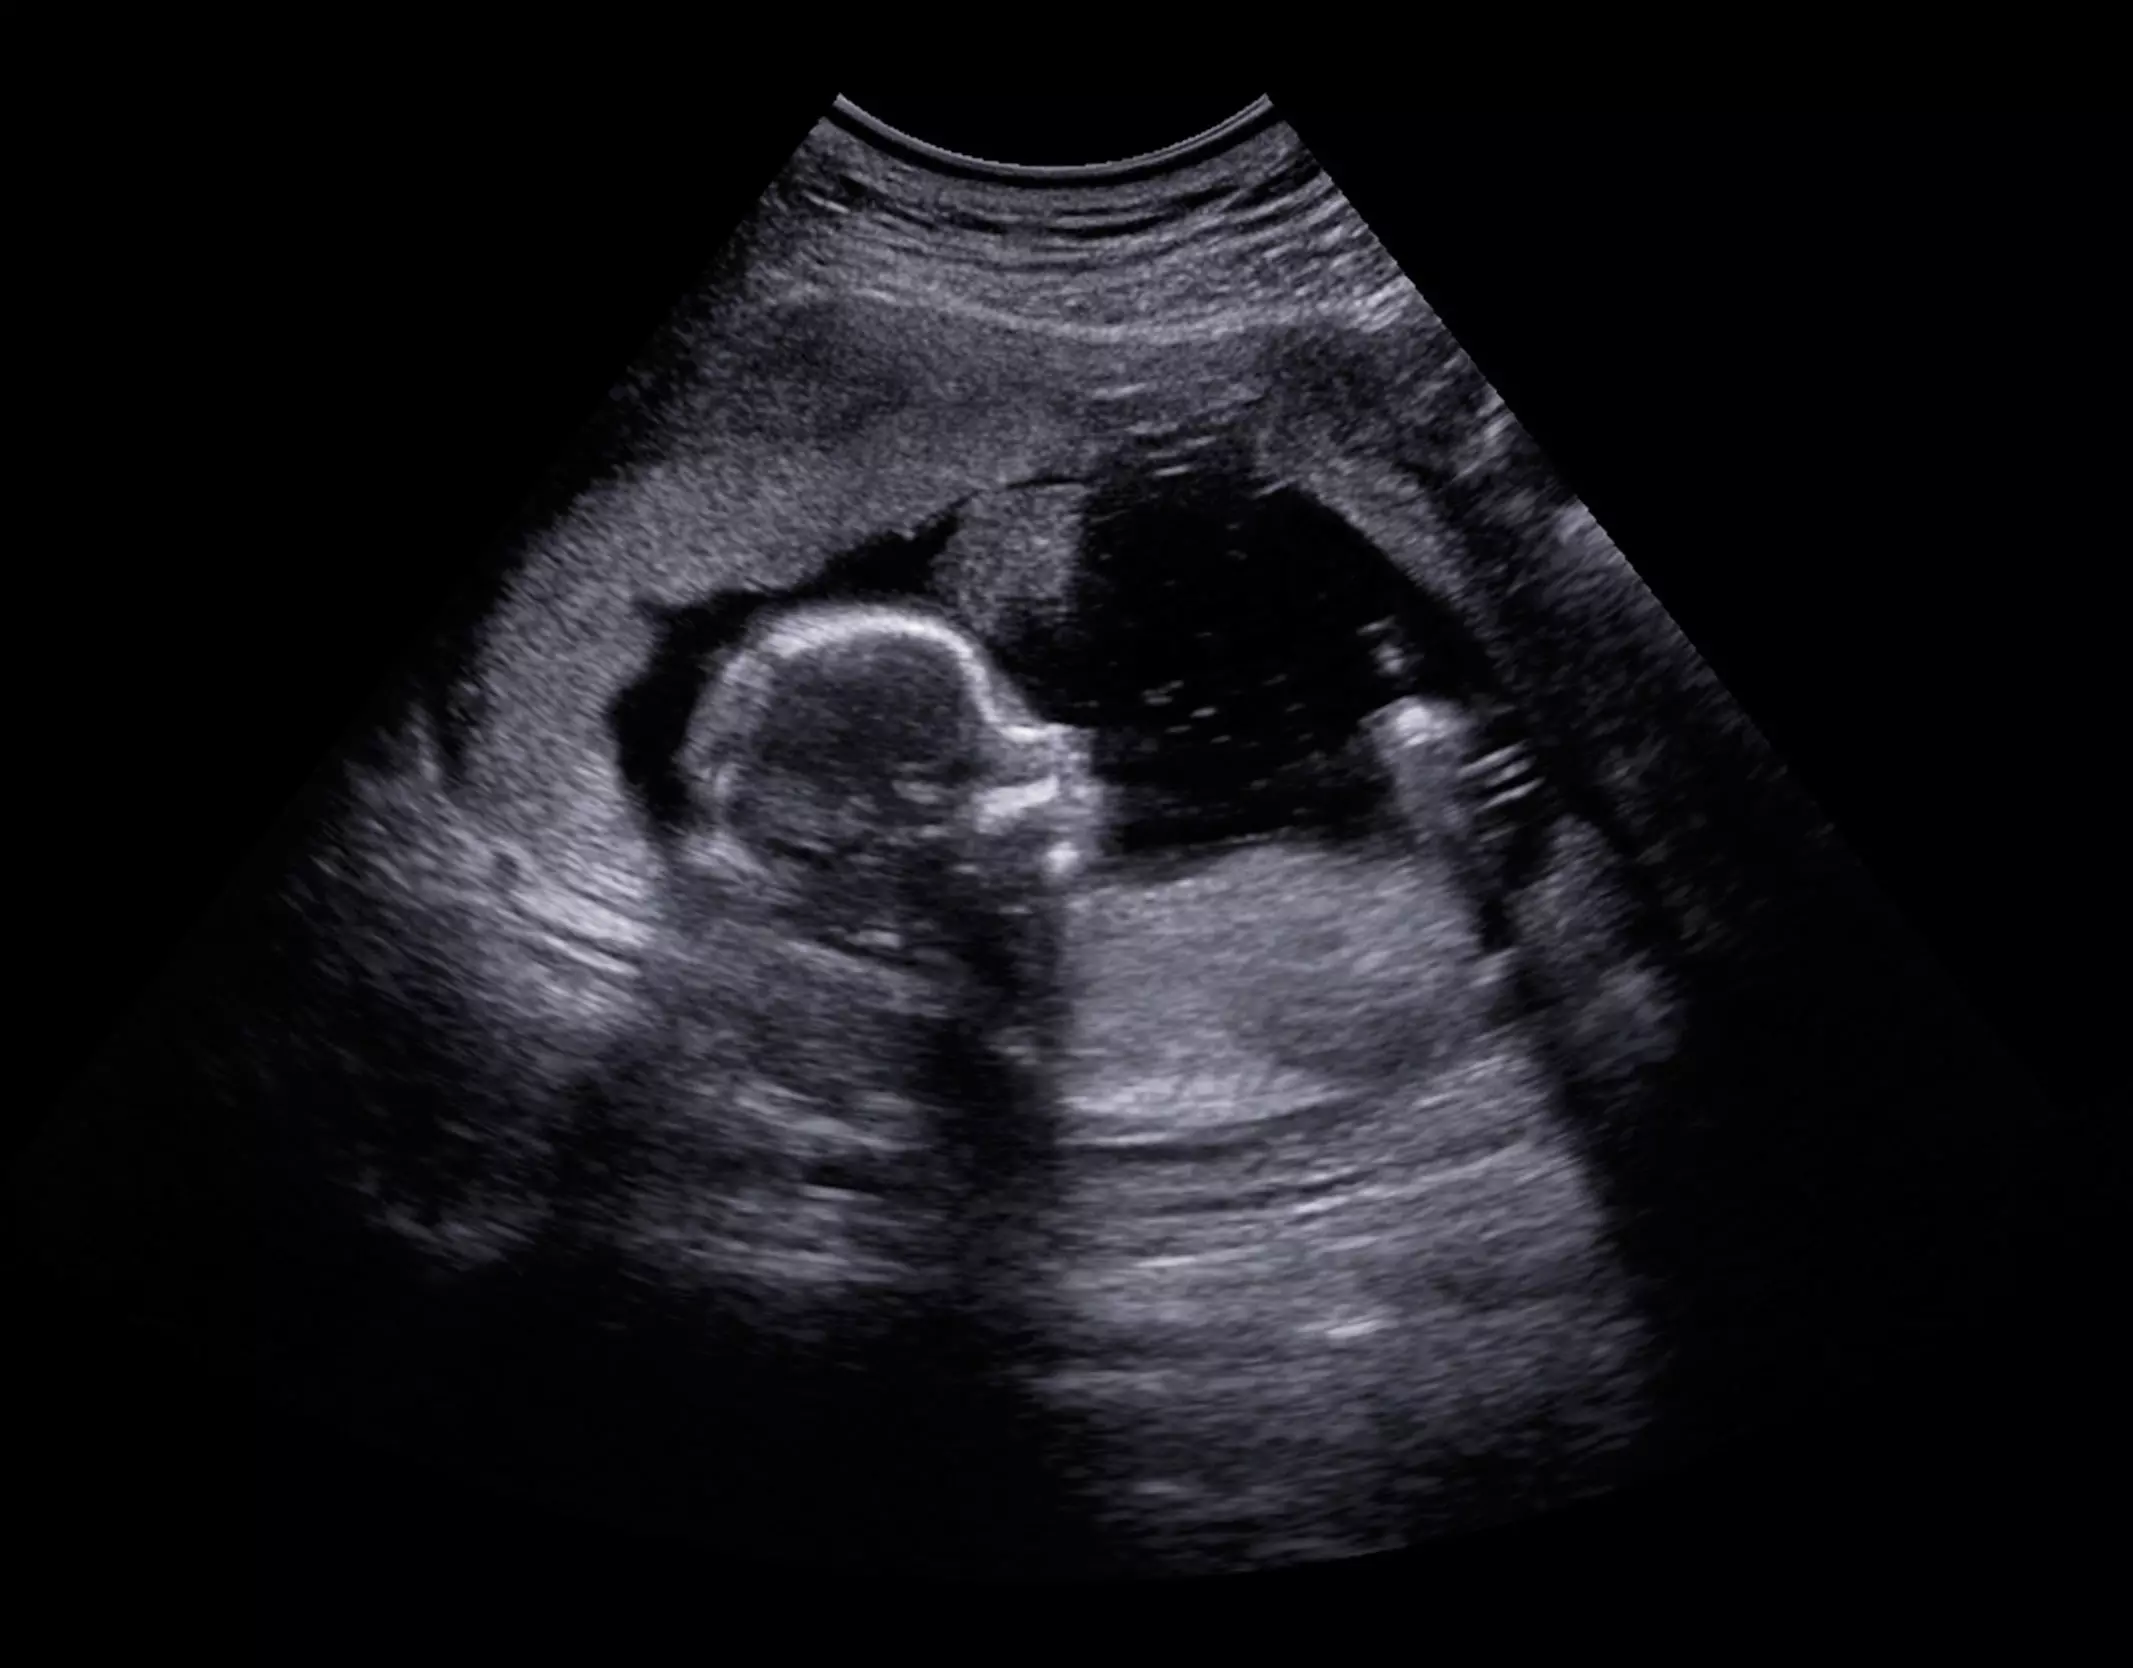

Later, he mentions that only <1% of those seeking the abortion pill have ectopic pregnancies, so ultrasounds aren’t an important factor when determining a woman’s eligibility for a medical abortion.

This is illogical. The abortion pill can kill a woman with an undiagnosed ectopic pregnancy. So, in order to avoid that possible outcome, shouldn’t every woman seeking the abortion pill be examined to make sure that she doesn’t have this potentially dangerous complication?

Perhaps his most interesting complaint is that the article talks about the humanity of the preborn. He wrote, “Of course the embryo is growing, that’s how pregnancy works, however they’re not fully formed in the first trimester. I’m curious, would you be willing to abolish all restrictions on abortions up to 10 weeks of pregnancy making it completely accessible earlier?”

So, is a human only a human when he or she is fully formed? Should we stop abortions after the baby can survive outside the womb? That’s probably not the point Dr. Grossman is trying to make, but doesn’t that mean we should make abortion illegal after the 21st or 22nd week of pregnancy? The baby is, for all intents and purposes, fully formed and can survive outside the womb with proper medical attention.